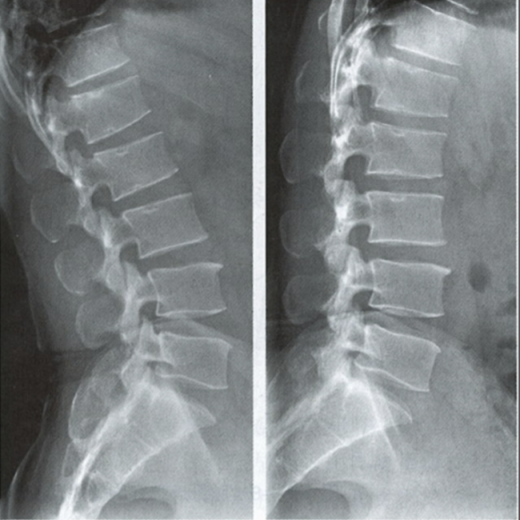

能屈能伸的腰椎——腰椎动力位

腰椎动力位,也称为过屈过伸位,可以理解为两个极限体位下的侧位片,腰椎动力位通过做最大程度弯腰(过屈)和后仰(过伸)的动作拍摄侧位片,来观察腰椎在极限活动下的表现。如果说腰椎侧位片能静态体现椎体的解剖学结构、序列及生理曲度改变,那么腰椎动力位则是评估腰椎动态功能性的检查。

腰椎过伸位:是指腰部尽可能向后伸展,以双髋关节位支撑点,运动前后骨盆位置无改变。腰椎过伸时,向前的曲度大于生理曲度,上部向后倾斜。

腰椎过屈位:是指腰部尽可能向前弯曲,以双侧髋关节位支撑点,运动前后骨盆位置无改变。腰椎过屈的表现位向前的曲度减小、变直,上部向前倾斜。

当1度及以上的滑脱时才可以在普通腰椎侧位上观察到,而1度以下的滑脱或失稳则在普通侧位片上难以发现,这时候就需要借助腰椎动力位进行诊断。

腰椎动力位 左图为过伸位、右图为过屈位